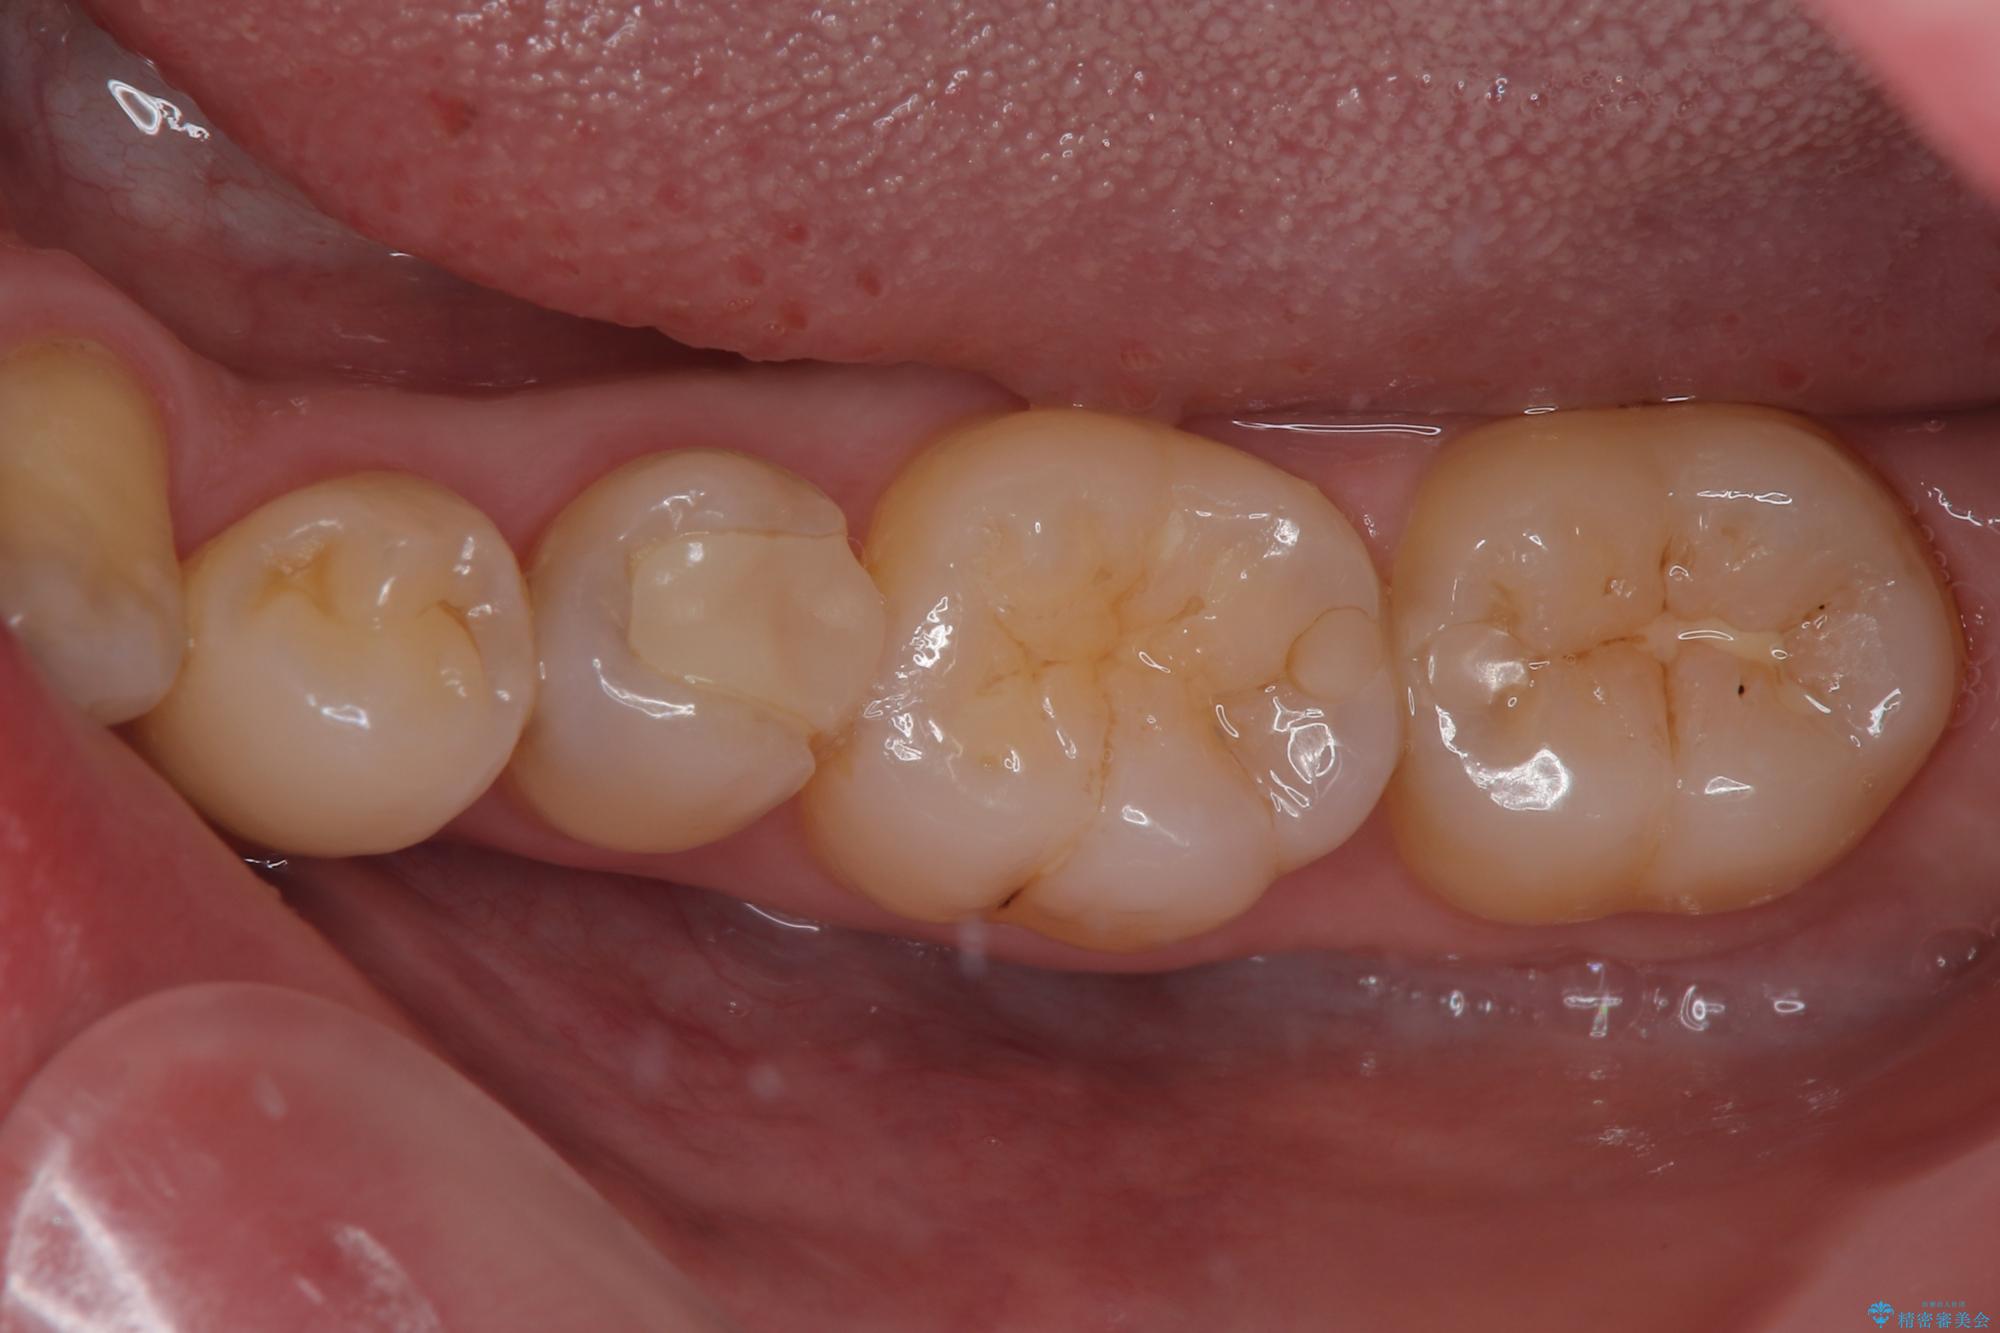

- 左下の奥歯のところがフロスが引っかかったり、ちぎれたりするとのことで来院された患者様です。検査の結果、神経は正常な反応を示し、フロスは引っかかる状態でしたので、虫歯治療も併せて行うためにオールセラミッククラウンによる補綴治療を行っていくことにしました。

拡大鏡視野下でプラスチックの詰め物、虫歯を除去しオールセラミッククラウンに適した形に整えました。

歯と歯茎の間に圧排糸と言われる糸を入れてシリコーン印象材にて型どりをしました。

フロスがちぎれることもなくなり、被せものが入っていることを忘れていたと大変喜んでいただきました。適合の良い被せものは二次的な虫歯の再発リスクを低減してくれます。